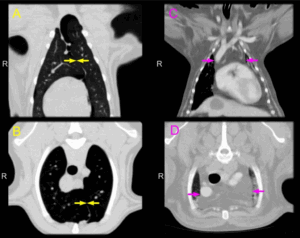

Наиболее информативным методом дифференциальной диагностики опухолевых и воспалительных изменений органов брюшной полости является мультиспиральная компьютерная томография (МСКТ). При этой методике визуализируются увеличенные, более 10—25 мм в поперечнике, лимфатические узлы неоднородной структуры (за счет периферического контрастного усиления и/или зон пониженной плотности), также характерно уплотнение перинодулярной клетчатки, прилежащей к пораженному лимфатическому узлу. При внутривенном контрастировании для туберкулеза характерным является накопление контрастного вещества по периферии лимфатического узла, в то время как его центральная часть, заполненная казеозными массами или жидким экссудатом, контрастное вещество не накапливает [13, 14]. Методы лучевой диагностики, как правило, позволяют визуализировать увеличенные лимфоузлы, но не установить этиологический фактор, что необходимо для дальнейшего лечения. Лапароскопия — наиболее точный и ценный метод диагностики поражения мезентериальных лимфатических узлов, позволяющий провести дифференциальную диагностику с другими ургентными заболеваниями брюшной полости при остром абдоминальном синдроме. Помимо визуальной оценки структуры и локализации измененных лимфатических узлов, МСКТ предоставляет возможность осуществить прицельную игольную или щипцовую биопсию и аспирировать имеющийся в брюшной полости экссудат для проведения лабораторных тестов [1, 2, 15, 16].

В 27 (27,8%) наблюдениях в брюшной полости пальпировались инфильтраты, состоящие из конгломератов увеличенных лимфатических узлов, расположенных в околопупочной и правой подвздошной областях, в 39 (40,2%) — в определялся асцит. Туберкулез легких верифицирован у 57 (58,8%) больных. При УЗИ брюшной полости в 82 (84,5%) наблюдениях визуализировались увеличенные, более 15—18 мм, лимфатические узлы, расположенные в корне брыжейки тонкой кишки и парааортально. По данным УЗИ, структура лимфатических узлов выглядела либо однородной, либо с зонами гипоэхогенных включений, что указывало на абсцедирующий характер процесса. При КТ-исследовании с внутривенным и пероральным контрастированием в 94 (96,9%) случаях также определялись увеличенные лимфатические узлы, расположенные преимущественно вдоль аорты, подвздошных сосудов и в корне брыжейки кишечника (рис. 1). Рис. 1. КТ органов брюшной полости в аксиальной плоскости. Конгломераты увеличенных забрюшинных лимфоузлов. Лимфатические узлы при КТ визуализировались как округлые структуры, были увеличены в размерах от 1 до 3 см и в большинстве наблюдений сливались в конгломераты, в 7 (7,5%) случаях они формировали крупные забрюшинные абсцессы. Структура увеличенных лимфоузлов была неоднородной за счет участков пониженной плотности различного размера, вплоть до тотального поражения (рис. 2). Рис. 2. КТ органов брюшной полости во фронтальной плоскости. Конгломераты увеличенных мезентериальных лимфоузлов. Полученные данные позволили установить наличие признаков увеличения в размерах и изменение структуры мезентериального и забрюшинного лимфатического аппарата, однако не помогли установить этиологию процесса. С целью уточнения причины болевого абдоминального синдрома и для этио-логической верификации диагноза произведена видеолапароскопия с биопсией лимфатических узлов. Во всех наблюдениях отмечались косвенные визуальные признаки увеличения лимфатических узлов, которые контурировались через истонченную брюшину в виде отдельных увеличенных округлых образований либо в виде конгломератов, оттесняющих тонкую кишку в сторону латеральных каналов. Инструментальная пальпация этих образований указывала на их плотную консистенцию (рис. 3). Рис. 3. Лапароскопия. Конгломерат лимфоузлов брыжейки тонкой кишки. Покрывающая их париетальная брюшина, как правило, была истончена, с инъекцией сосудов, в 19 (19,6%) случаях на брюшине имелись плотные бугорки белесоватого цвета до 3—6 мм в диаметре, характерные как для туберкулеза брюшины, так и для канцероматоза. В 2 (2,1%) наблюдениях, помимо визуальных признаков забрюшинной лимфаденопатии, были выявлены признаки вторичного перитонита с гноевидным выпотом. У 37 (38,1%) пациентов в брюшной полости обнаружен серозный выпот в количестве от 150 до 2700 мл. У 3 (3,1%) больных выявлены забрюшинные образования опухолевой природы, оттесняющие петли тонкой кишки и также сопровождающиеся выпотом и признаками увеличения мезентериальных лимфатических узлов.